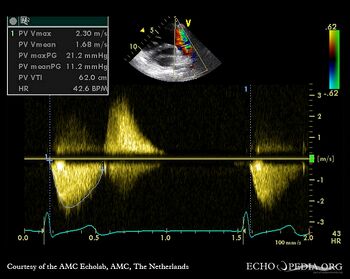

| PSAX with Color Doppler: dilated pulmonary artery in Marfan patient | Continuous-wave signal of transpulmonary flow |